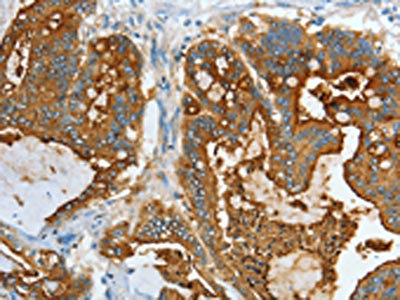

The image on the left is immunohistochemistry of paraffin-embedded Human colon cancer tissue using CSB-PA160116(CEACAM5 Antibody) at dilution 1/20, on the right is treated with fusion protein. (Original magnification: ×200)